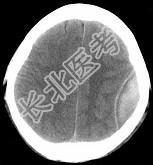

- 单项选择题男性,25岁, 外伤后行CT检查,最可能的诊断为 ( )

A、左顶枕部硬膜下血肿

B、左顶枕部硬膜外血肿

C、左顶枕叶出血

D、脑挫裂伤

E、脑膜瘤